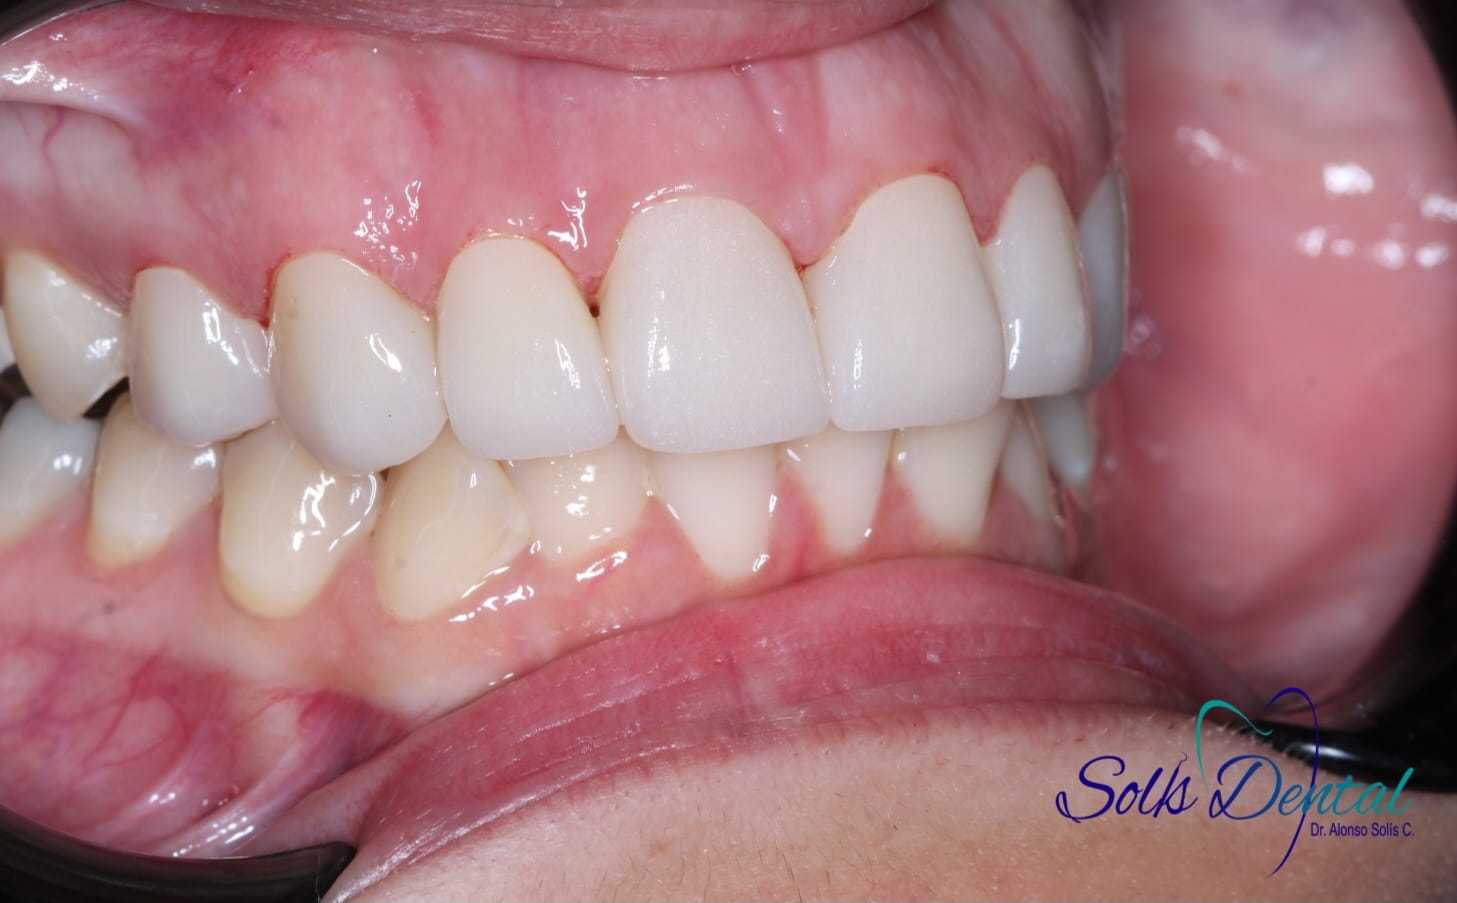

Caso 5

Se realizan Coronas dentales en Ziconio para mayor resistencia,mejorar armonia y estética, en piezas con resinas desajustadas y caries recidivas.